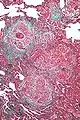

![]() صورة مجهرية بتكبير عالٍ تظهر عينة من رئة مريض مصاب التهاب الحساسية الزائدة المزمن، يلاحظ وجود توسع طفيف في جدار الحويصلات بفعل الخلايا اللمفاوية. وجود خلية عملاقة متعددة الأنوية في النسيج الخلالي يعد أحد الظواهر التي تؤكد على صحة التشخيص

. صورة مجهرية بتكبير عالٍ تظهر عينة من رئة مريض مصاب التهاب الحساسية الزائدة المزمن، يلاحظ وجود توسع طفيف في جدار الحويصلات بفعل الخلايا اللمفاوية. وجود خلية عملاقة متعددة الأنوية في النسيج الخلالي يعد أحد الظواهر التي تؤكد على صحة التشخيص

يمكن لخزعات الرئة ان تكون تشخيصية في حالات التهاب الحساسية الزائدة المزمن، أو قد تساعد على اقتراح التشخيص أو تؤدي لاكتشاف أو تكثف البحث لاكتشاف المادة مثيرة للحساسية. والميزة الرئيسية لالتهاب الحساسية الزائدة المزمن في الخزعات الرئوية هو التوسع في النسيج الخلالي بواسطة الخلايا الليمفاوية مترافقه مع الخلايا العملاقة متعددة النوى عرضية أو الناتج بسبب الورم الحبيبي السائب..[8][9]